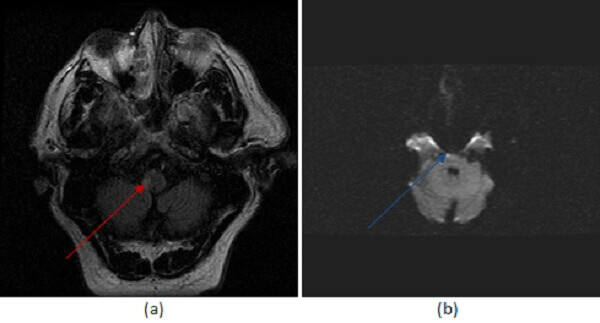

Figure 1: (a, red arrow) FLAIR images demonstrate increased signal involving the right lateral medulla (b, blue arrow) diffusion weighted imaging demonstrates focal increased signal in a smaller portion of this territory consistent with an acute or early subacute infarct.

The lateral medullary syndrome has specific clinical symptoms which include contralateral loss of pain and temperature sensation in the body with ipsilateral loss in the face. Additional symptoms include ataxia, swallowing and taste disorder through involvement of the ninth cranial nerve and Horner’s syndrome (ptosis, myosis and anhydrosis) through involvement of descending sympathetic fibers.